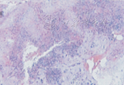

术后病理结果显示7个病种:感染性疾病6例[慢性或亚急性骨髓炎4例(典型病例见图1、图2),结核2例(典型病例见图3、图4)],骨血管瘤2例(典型病例见图5、图6),骨囊肿、骨软骨母细胞瘤、骨纤维结构不良、骨样骨瘤各1例。12例患儿的一般资料、实验室检查、影像学特点及病理诊断结果见表1。

骨质破坏是局部骨质为病理组织所代替而造成的骨组织缺失,常为肿瘤、炎症等直接或间接引起破骨活动增强的结果。当骨破坏吸收超过30%以上时X线才可显示。CT扫描能清楚显示距骨病变的位置、边界、形态、密度(是否有脂肪成分、坏死液化、钙化和骨化),周围结构受推移、压迫或侵犯情况。通过测量病灶的CT值,判断其成分。MRI对软组织肿块显示更为敏感,对距骨骨髓信号极其敏感,利用脂肪抑制T2WI与T1WI序列,能根据病灶的信号判断其成分,显示病灶内有无纤维分隔、病灶周围有无骨髓水肿、早期未骨化的骨膜异常。由于距骨体积较小,主要由松质骨组成,骨皮质较薄,当发生骨质破坏时易骨内侵蚀并可突破骨皮质及骨膜侵袭到关节及周围软组织。由于儿童距骨骨质破坏病变类型具有多样性,其影像学表现往往不如长骨上典型,相应的影像学表现也具有多样性和相似性,在诊断及鉴别诊断上均有一定难度[8]。本组12例患儿影像学表现的共同特征是距骨不同形态的骨质破坏,但不同原因引起的骨质破坏,由于病变的性质、发展的快慢和邻近骨质的反应性改变不同,有对应不同的影像学特点。结合病理诊断结果,本研究回顾性分析12例患儿的影像学表现:距骨慢性或亚急性骨髓炎影像学表现为距骨体骨质破坏周围常有明显的增生、硬化[9,10,11];距骨结核X线片表现为示距骨骨质明显破坏,2例患儿均未见新骨形成[12];本组1例骨样骨瘤CT表现为距骨颈皮质下方低密度瘤巢,周围有硬化环。1例距骨纤维结构不良患儿X线表现为囊状病灶,MRI T1WI病灶呈等信号,T2WI呈高信号为主,边缘呈低信号硬化;1例骨囊肿CT值呈液体密度,X线表现为类圆形低密度灶,位于距骨体;距骨软骨母细胞瘤CT及MRI检查显示低密度囊性变,溶骨性破坏,骨小梁模糊,边界清楚,可见薄的硬化边,易与骨囊肿混淆。